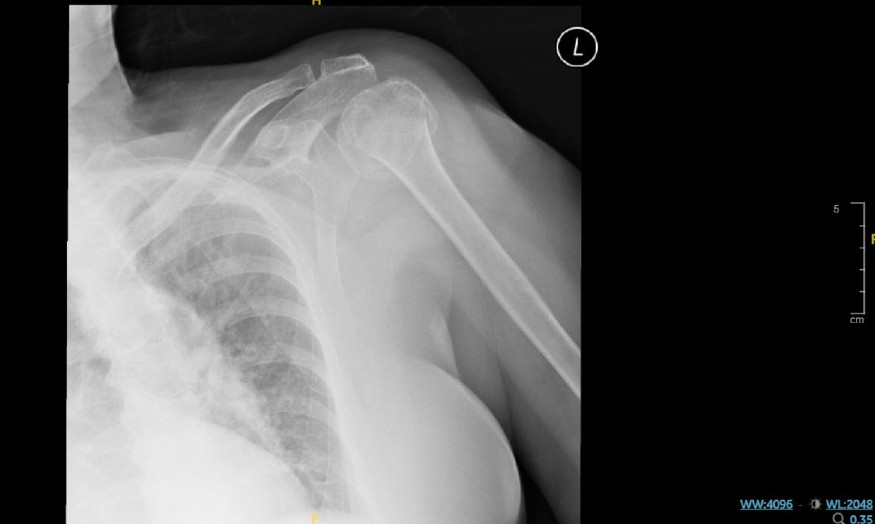

- Fell in January 2023 and sustained multiple fractures: vertebral, left proximal humerus, and right lateral malleolus.

- Imaging confirmed fractures involving L1, left proximal humerus, and right lateral malleolus. All were managed non-operatively.

X-ray